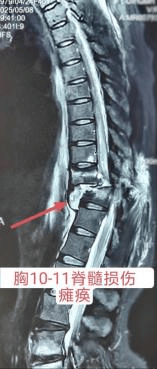

近日,西安市红会医院神经外科赵东升主任团队为一名因胸段脊髓损伤导致下肢瘫痪,感觉及运动消失,大小便无知觉的患者实施了脊髓电刺激双外科电极植入术,患者术后恢复良好,其感觉功能和运动功能均有所提升。 病例